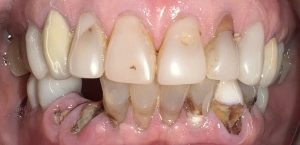

Patient with missing teeth and full mouth of infection & decay seeking help of a biological dentist

The patient presented to Virginia Biological Dentistry for a comprehensive biological evaluation after experiencing extensive dental breakdown and ongoing infection. Examination revealed advanced decay in the upper dentition, missing teeth, and widespread infection affecting all remaining lower teeth, rendering the lower teeth non-salvageable.

Cavities and Infections and broken teeth